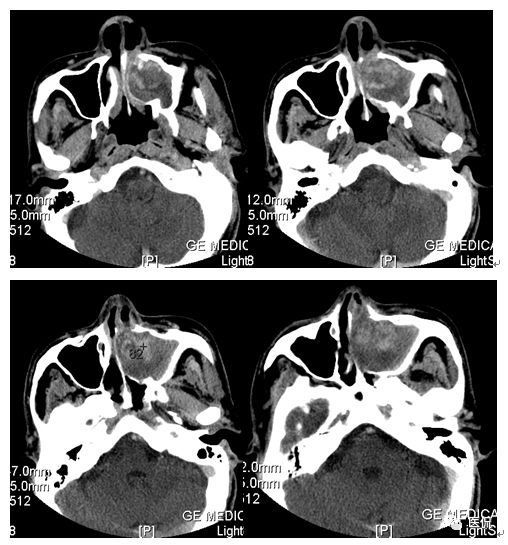

CT平扫及增强示:左侧上颌窦及鼻腔可见软组织密度影,呈膨胀性生长,周围骨质压迫性吸收破坏,累及左眶,病灶密度不均匀,周边区可见点状钙化,增动脉期轻度强化,局部见小灶性稍高密度区,静脉期病灶内见不均匀明显强化,CT值最高达117HU,延迟期强化范围有所增大。

本例病灶较大,周围骨质可见吸收破坏,并累及眼眶,病灶内少量钙化,增强扫描具有一定特征性,表现为动脉期轻度强化,局部见小灶性稍高密度区,静脉期病灶局部呈明显强化,CT值最高达117HU,延迟期强化范围有所增大,呈延迟渐进性强化的特点,推测为病灶内出血所致。